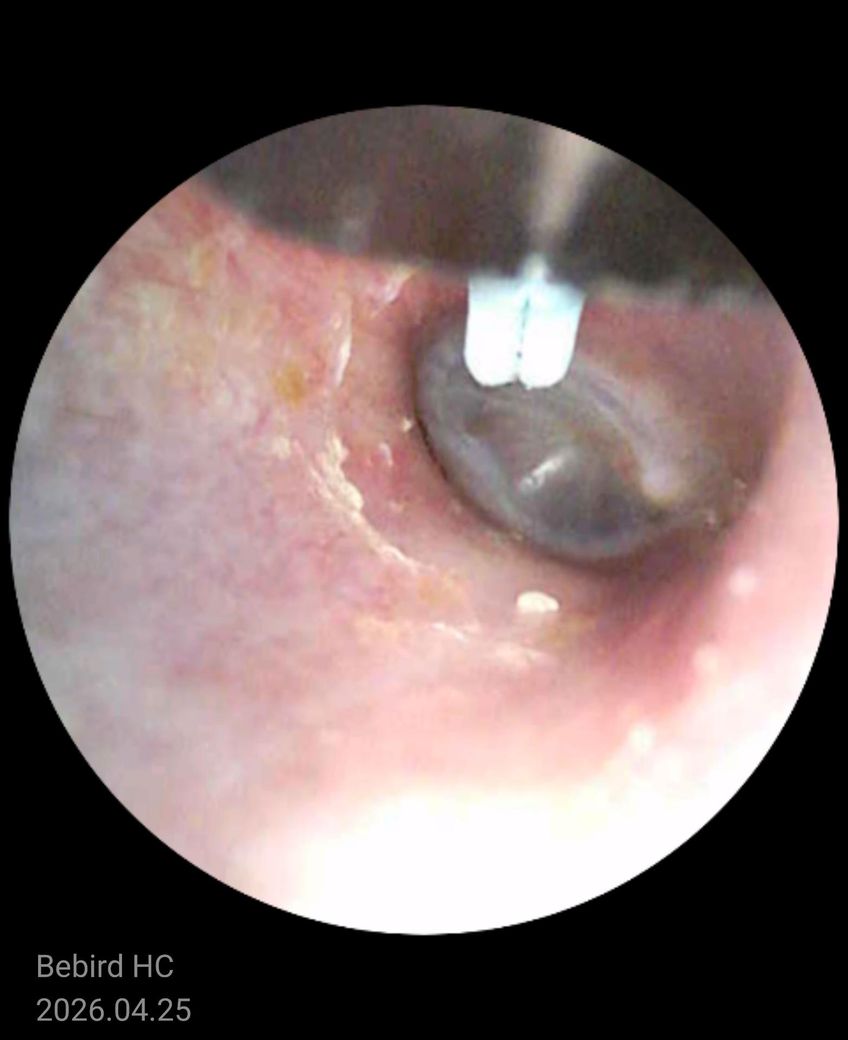

사진상 고막은 회색빛으로 유지되어 있고 뚜렷한 천공이나 심한 발적, 삼출(고름)이 차 있는 전형적인 중이염 소견은 보이지 않습니다. 대신 외이도 피부가 자극된 흔적과 이물(귀지, 각질)이 일부 보이며, 가려움·간헐적 통증·먹먹함이라는 증상 조합은 외이도염 또는 외이도 피부염 양상에 더 가깝습니다.

병태생리적으로는 귀를 자주 만지거나 이어폰 사용, 세정 과다 등으로 외이도 피부 장벽이 손상되면 가려움이 먼저 생기고, 2차로 염증이 생기면서 통증이나 먹먹함이 동반될 수 있습니다. 귀지와 각질이 고막 근처에 붙어 있으면 일시적인 이명이나 막힌 느낌도 유발할 수 있습니다.

중이염이라면 보통 지속적인 통증, 청력 저하, 발열 또는 고막 뒤 액체가 보이는 소견이 동반되는 경우가 많습니다. 현재 사진과 증상만으로는 가능성이 낮은 편입니다.

정리하면, 현재는 중이염보다는 외이도 피부 자극 또는 외이도염 가능성이 높고, 자극을 줄이고 필요 시 점이약 치료로 호전되는 경우가 많습니다.